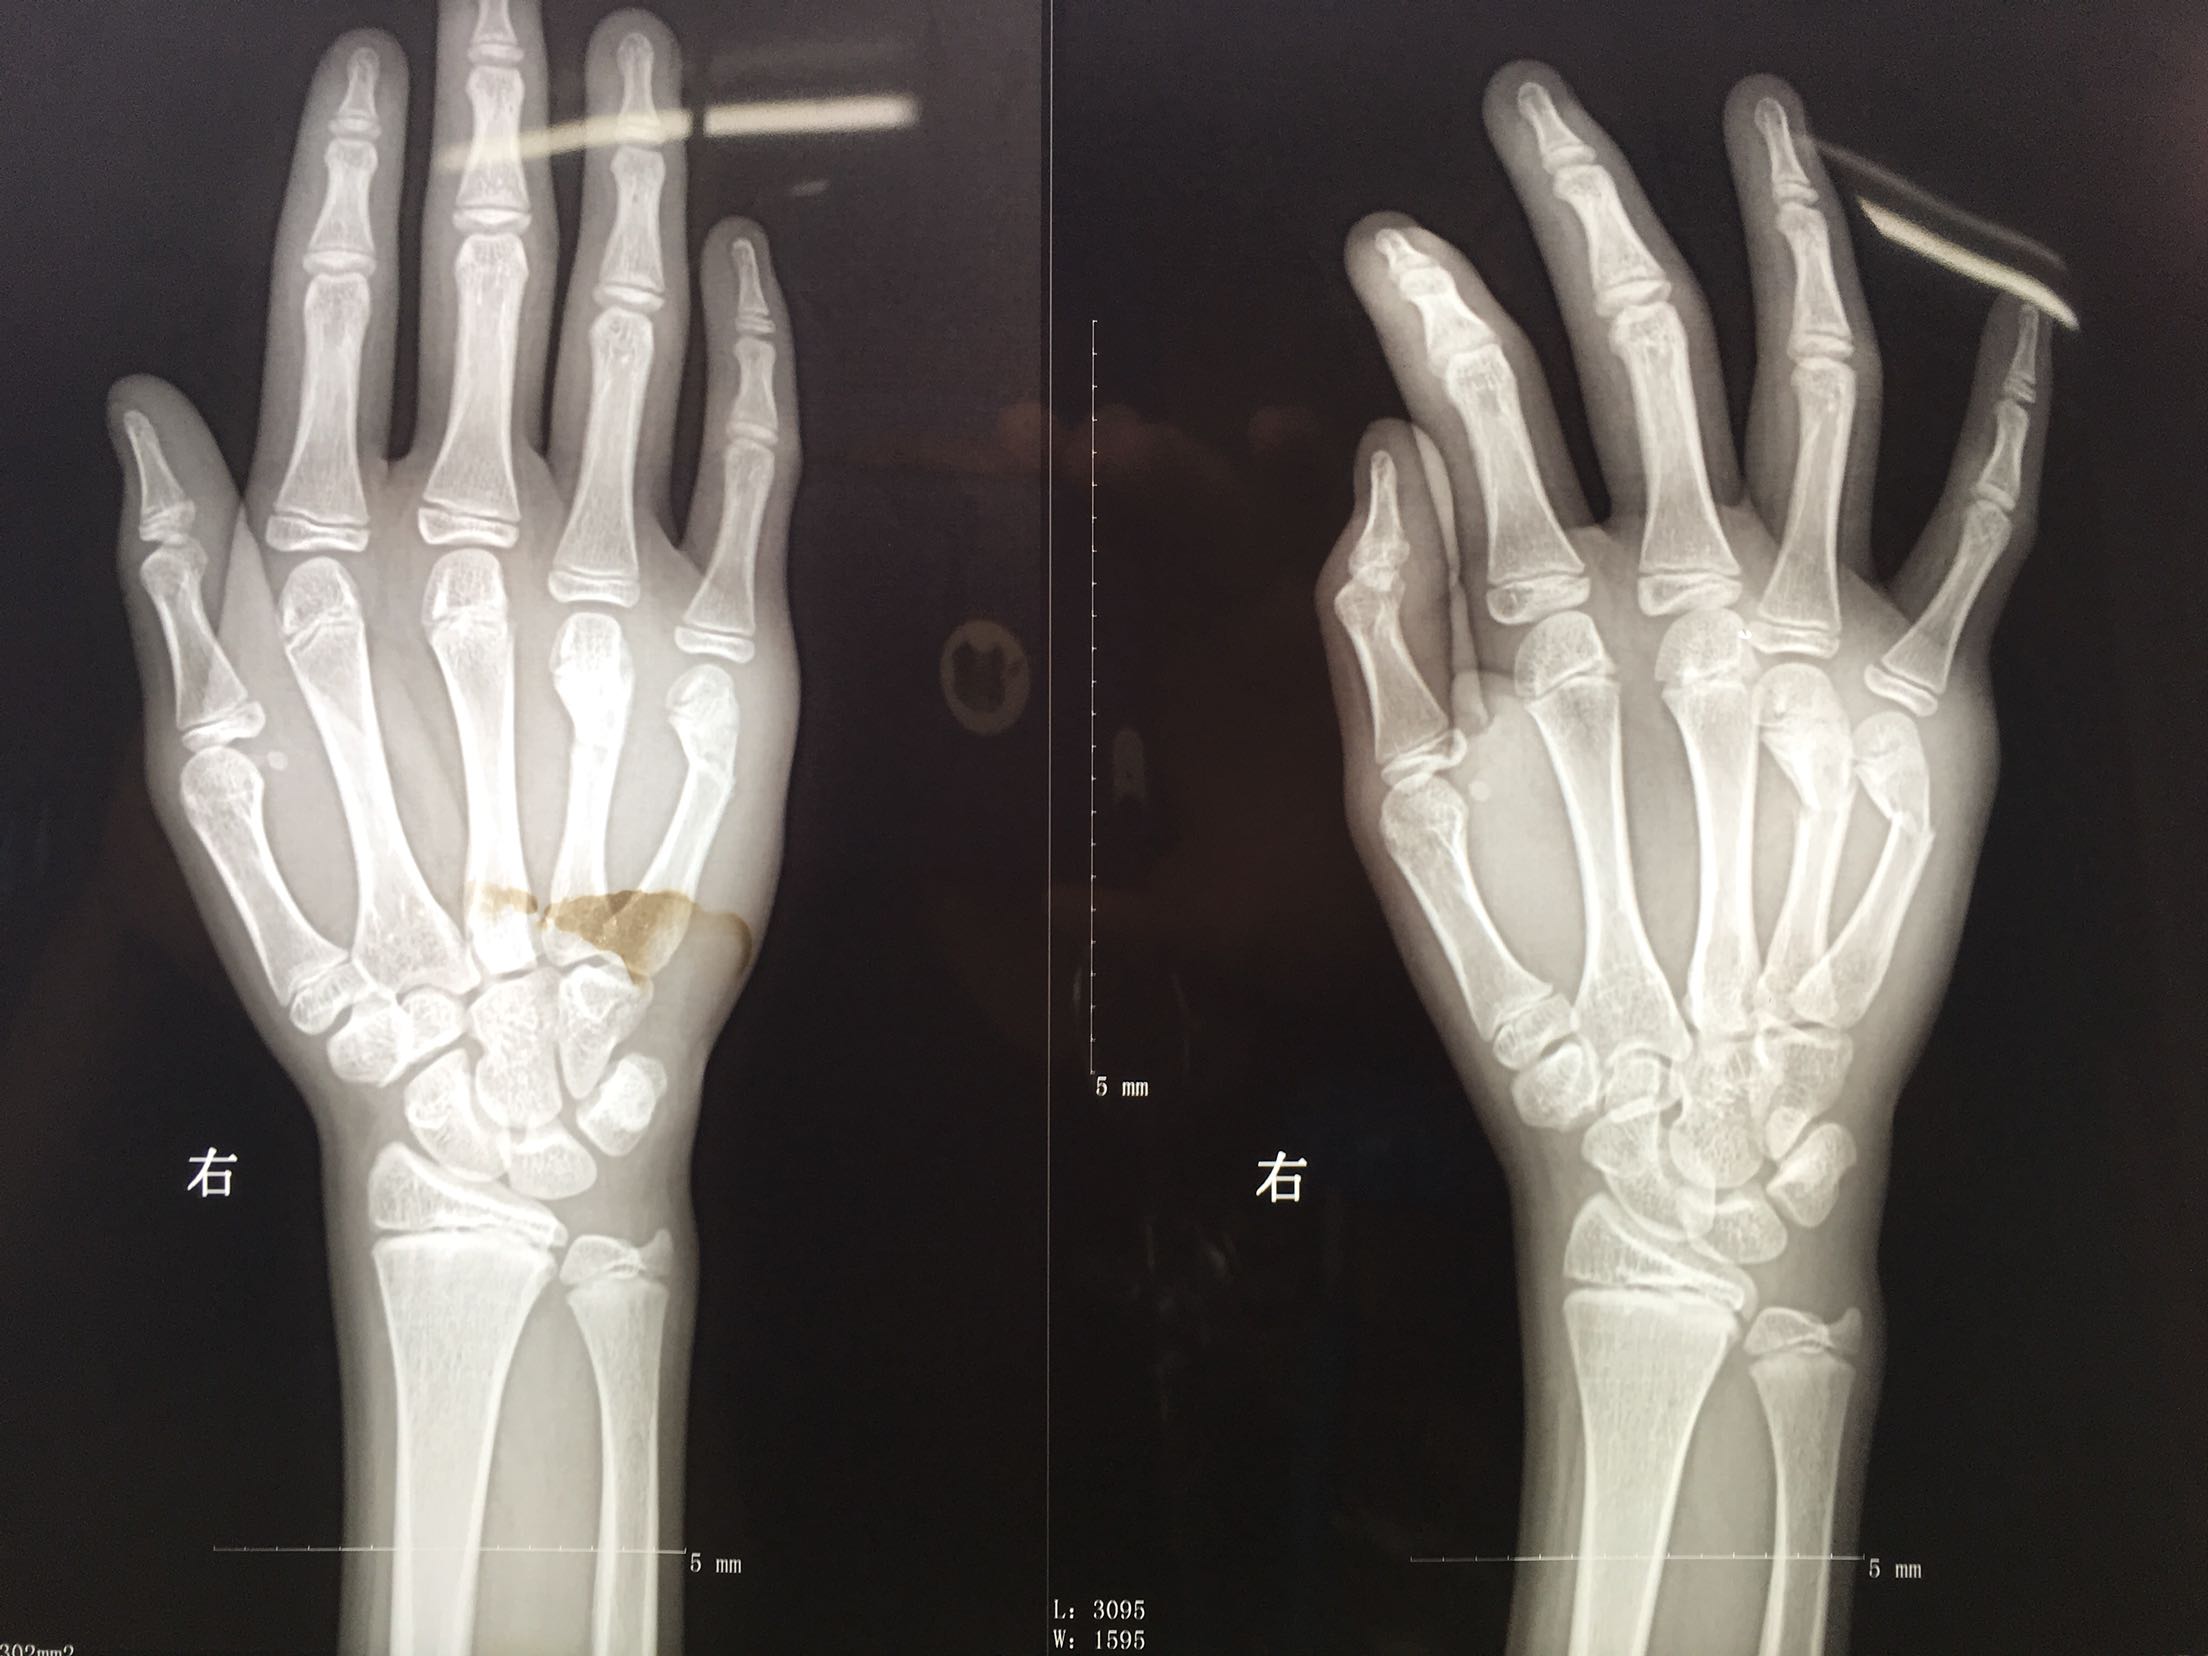

右第四,五掌骨骨折(微创)

患者,男,13岁,撞伤后右手肿痛,活动受限1天入院。

右手肿胀明显,局部皮色青紫,皮温稍高,第四,五掌骨头处压痛,纵叩痛阳性,掌指关节活动受限,末梢血运感觉正常。

完善检查,在臂丛麻醉下行闭合复位内固定术,术后抗炎,消肿止痛等对症处理,右手石膏托制动。